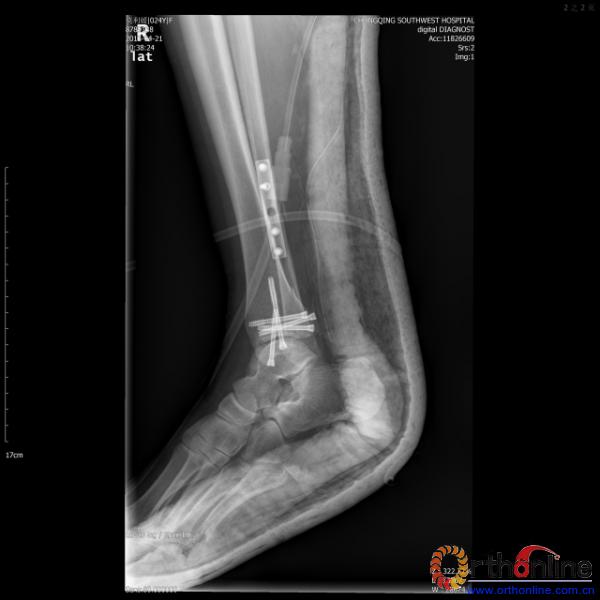

伤员和家属迅速赶到西南医院,10点关节外科段小军副教授查看伤员后急诊收入院,拍摄X片和急诊行三维CT重建检查,提示踝关节创伤严重,出现三踝骨折伴胫距关节脱位,需要急诊手术治疗。随后段教授与正在四川成都参加“汶川地震5周年灾害医学救治研讨会”的杨柳主任联系,进一步完善救治方案。地震当晚,段教授为该伤员进行急诊手术,手术顺利对复杂骨折进行了解剖复位,有效的钢板螺钉固定。术后伤员的疼痛明显缓解,复查X片,踝关节结构恢复满意。

患者术后X片(二)